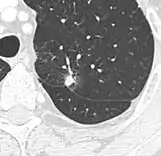

For cases suspicious enough to proceed to biopsy, small biopsies can be obtained by fine needle aspiration or bronchoscopy are commonly used for diagnosis of lung nodules.[19] CT guided percutaneous transthoracic needle biopsies have also proven to be very helpful in the diagnosis of SPN.[6]

In selected cases, nodules can also be sampled through the airways using bronchoscopy or through the chest wall using fine-needle aspiration (which can be done under CT guidance). Needle aspiration can only retrieve groups of cells for cytology and not a tissue cylinder or biopsy, precluding evaluation of the tissue architecture. Theoretically, this makes the diagnosis of benign conditions more difficult, although rates higher than 90% have been reported.[20] Complications of the latter technique include hemorrhage into the lung and air leak in the pleural space between the lung and the chest wall (pneumothorax). However, not all these cases of pneumothorax need treatment with a chest tube.[21]